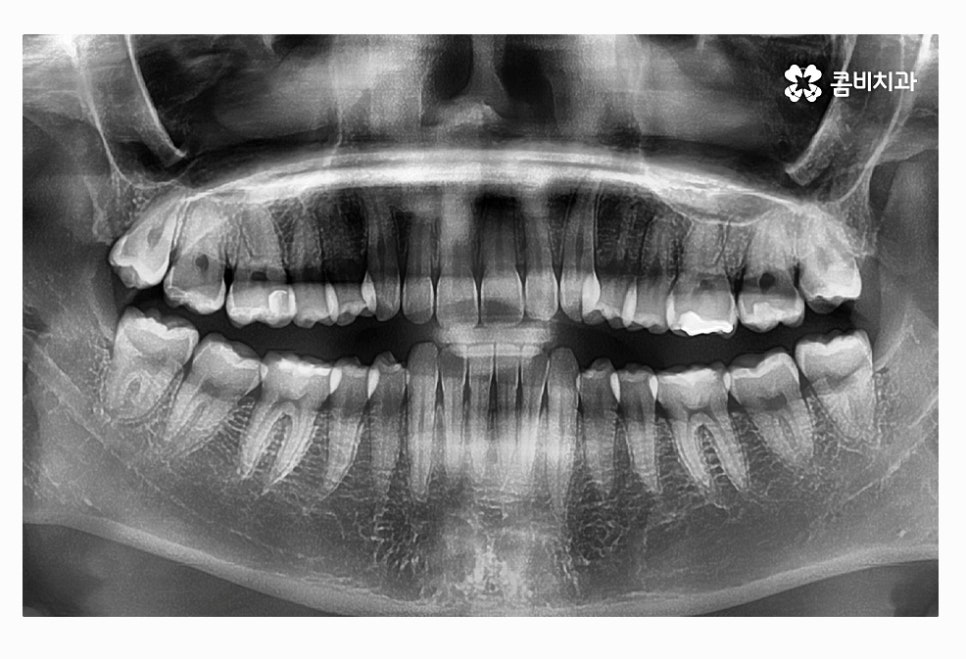

오늘 여러 사례에서 보신 것처럼 사랑니는 다양한 형태로 자라며

꼭 충치가 아니더라도 구강 건강에 악영향을 주는 사례가

많기 때문에 당장 발치를 하는 것을 고민하기보다는

주기적으로 사랑니 상태를 검진하고 스케일링을 통해

청결 관리를 잘하는 것이 큰 문제로 이어지는 일을 막을 수 있어요.

사랑니의 위치와 자라는 방향이 좋지 않은 경우에

평생 건강하게 지켜야 할 어금니의 손상과 수명을

줄어들게 할 수 있기 때문에 발치 시기를 미루지 말고

필요한 경우 의사와 잘 상의하셔야 하며